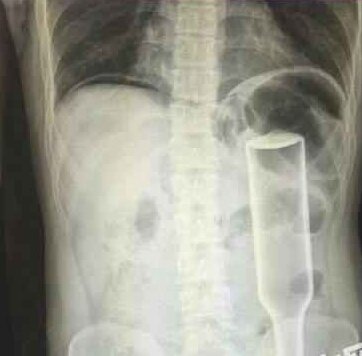

【男子为求刺激将花露水瓶插入菊花,戳破肠子险致命】郑州务工的男子王某,下班到家后闲着没事儿干,将一个长18厘米的花露水瓶子塞进自肛门,不料因为用力过猛,快感没来,瓶子却把直肠给戳破了,疼得受不了,王某羞答答地来到郑州人民医院就诊,医生给他做了手术,现在已经出院。